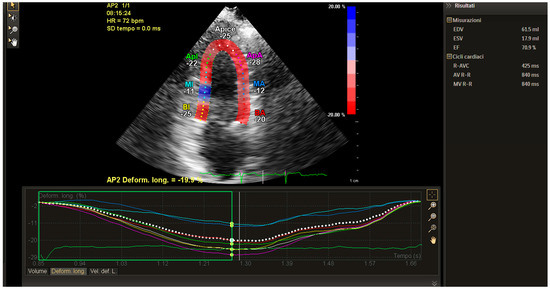

2. Technical Considerations for Strain Analysis

3. Clinical Applications of Strain for the Early Clinical Detection of Myocardial Damage

4. Strain in Cardio-Oncology